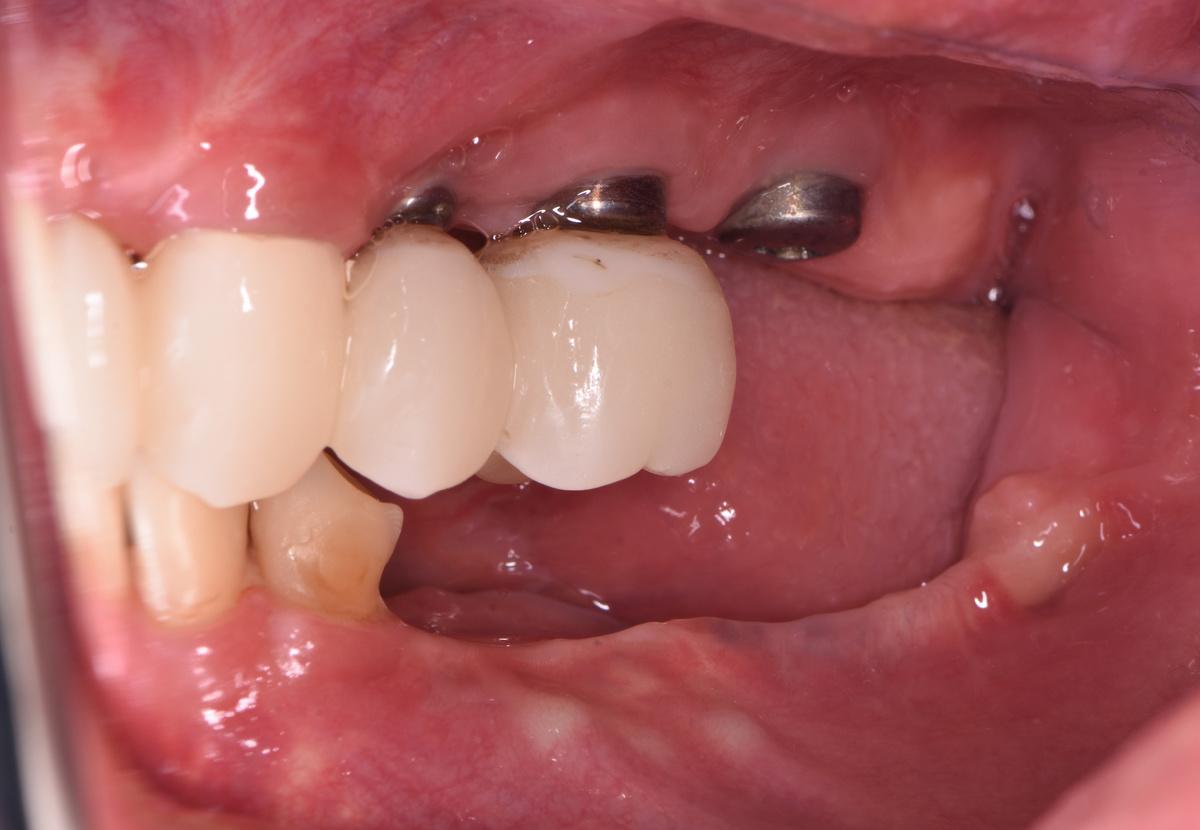

Слева. 4 коронки с опорой на 4 импланта + зуб мудрости

Слева. 1 свой зуб под коронкой, 2 коронки с опорой на 2 импланта + дистопированный зуб мудрости

Диагностика и клиническая картина

На рентгеновском снимке ситуация в полости рта выглядит следующим образом:

Проблемы:

1 — атрофия костной ткани в области ранее удаленных 5 и 6 зубов на верхней челюсти справа.

2 — атрофия костной ткани до первого витка имплантов в области 4, 5 и 6 зубов на верхней челюсти слева

3 — внушительный «карман» между зубом мудрости и коронкой на импланте, проведение гигиены которого в домашних условиях было невозможно

4 — выраженная атрофия костной ткани, убыль десны, оголение имплантатов, воспаление, гноетечение

5 — экстремальная атрофия костной ткани в области импланта 5-ого зуба, воспаление мягких тканей, гноетечение

6 — симметричный «карман» слева, между зубом мудрости и коронкой на импланте

7 — клиновидные дефекты (абфракции) и закономерная рецессия (опущение) десны

Позитив:

Сохранившиеся зубы во фронтальном отделе, и снизу, и сверху, подарили нашей героине последний шанс восстановить зубы без искусственной розовой десны